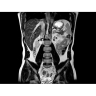

МРТ аппарат GE Optima MR450w 1.5T

МР-томограф с широким туннелем Optima MR450w является настоящей рабочей лошадкой и может эффективно обслуживать большее число пациентов. Томограф обеспечивает одновременно удобство пациента, продуктивность работы, отличное качество изображения. В этой МРТ-системе инженерам компании удалось без компромиссов совместить необходимый объем перемещения с удивительно высоким качеством изображения.

«Правильные возможности», «Правильные условия», «Правильные инвестиции» — под таким девизом компания GE Healthcare представляет свой МР-томограф с широким туннелем Optima MR450w.

Благодаря принципиально новым технологиям мы расширили возможности МР-томографов с широкими туннелями, совместив непревзойденное качество изображений с высокой производительностью при широком — 50 см — поле зрения.

• Широкое поле зрения — поле зрения шириной 50 см позволяет охватывать крупные анатомические области за меньшее число сканов.

• Визуализация всего позвоночника слиянием двух участков — получить изображение всего позвоночника можно намного быстрее.